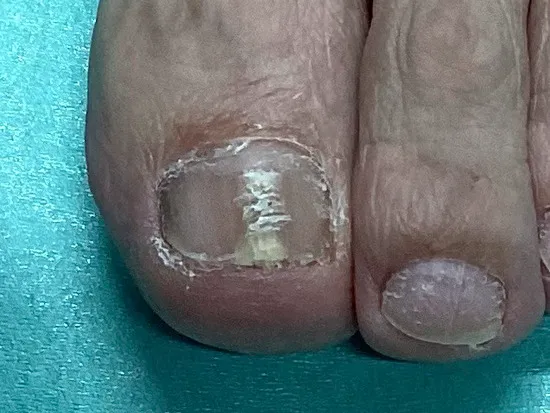

爪白癬(爪の水虫)の症例画像